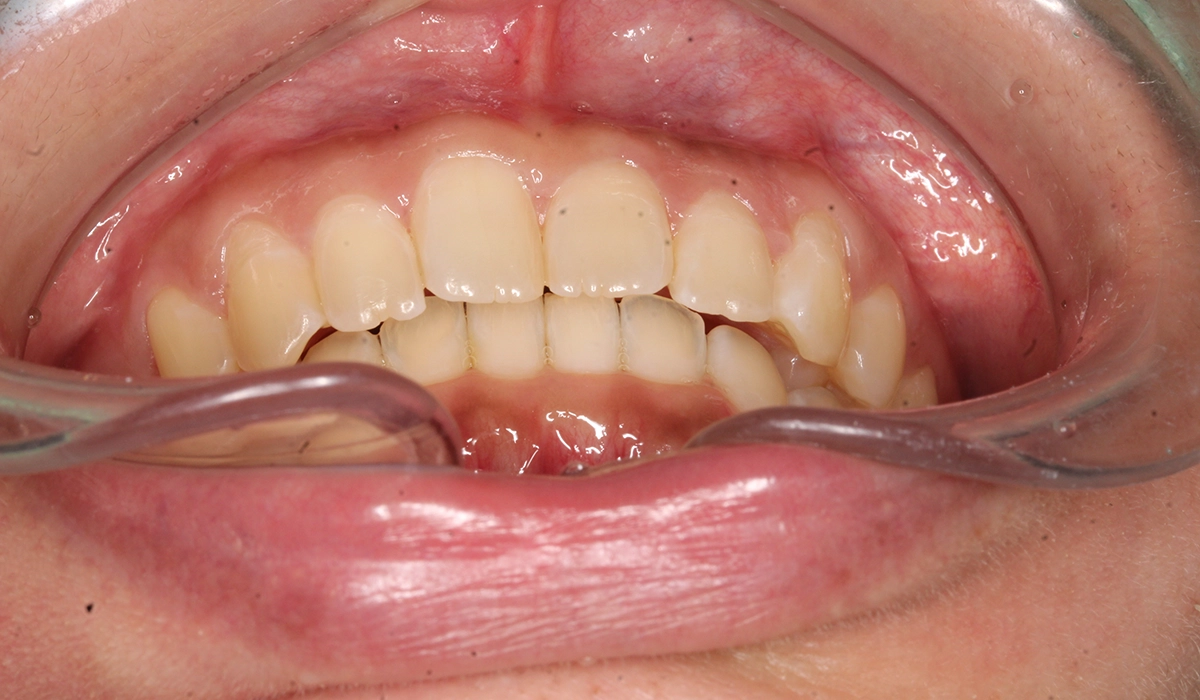

今回ご紹介する患者様は、前歯の噛み合わせの悪さ、歯並び、下の前歯が上の歯茎に当たることを気にされており、矯正検査後叢生Ⅰ級と診断いたしました。

術後:正面

| 主訴 | 前歯の噛み合わせ・歯並びが気になる |

| 治療期間 | 4カ月 |

| 治療費用 | 935,000円(税込) |

| 治療内容 | 前歯の噛み合わせの悪さ、歯並び、下の前歯が上の歯茎に当たることを気にされており、矯正検査後叢生Ⅰ級と診断いたしました。 |